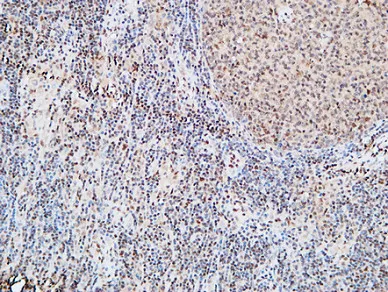

HDC Rabbit Polyclonal Antibody

Cat: APRab11956

Size1:50μl Price1:$118

Size2:100μl Price2:$220

Size3:500μl Price3:$980

Size2:100μl Price2:$220

Size3:500μl Price3:$980